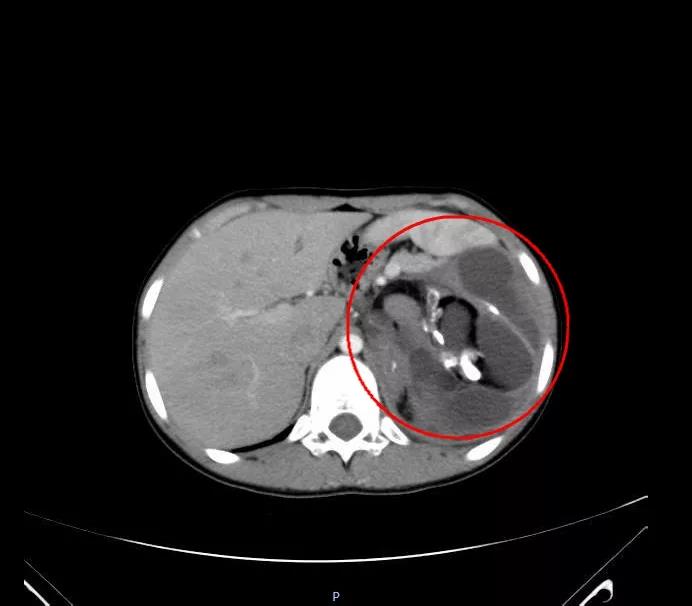

做完全腹CT檢查后,她被告知腹腔有一大包塊。這個包塊存于腹膜后,經(jīng)過多年吸附腹主動脈營養(yǎng)已長至10多公分,且將胰腺和脾臟擠至胸腔邊緣。最有意思的是,這個包塊竟有頭發(fā)、骨骼等組織,極像畸形的胎兒。